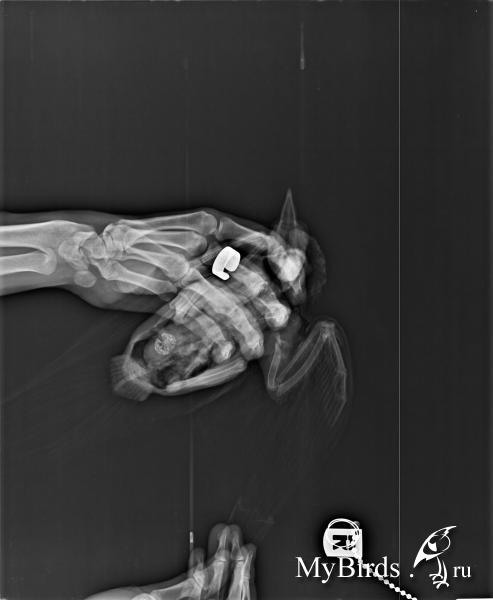

Перелом в облати плечелопаточного сочленения.. На волю не полетит никогда уже вероятнее всего. Рентгеньте в спинной проекции, локализация и по Вашим описаниям наводит на мысль о пуле. Нужно исключить/подтвердить вариант нахождения их в тканях птицы. Если есть, обязательно хирургически удалять, в противном случае - медленное свинцовое отравление с постепенным отказом почек в течение ближайших месяцев/пары лет.

Травматин уже нет смысла, поздновато. На фото костная мозоль видна сформированная.

Спасибо всем за ответы! Удалось сделать рентген в другом городе :)) Показания рентгена - наличие костной мозоли, и врач сказала, что был перелом еще в одном месте, кости еще срастаются. Пули и прочих инородных предметов, к счастью, нет. В остальном голубь по-прежнему бодр, требует свободы, хорошо кушает. :)) Опухоль стала немного меньше. Так что пробуем травматин.

Вы рентген-снимок сфотографируйте и выложите, врач же Вам по органам комментариев не дал на рентгене. А так посмотрим заодно общее состояние.

Только написала, как удалось добраться до дисковода. Вот что есть.

post-55237-1401174159_thumb.jpg